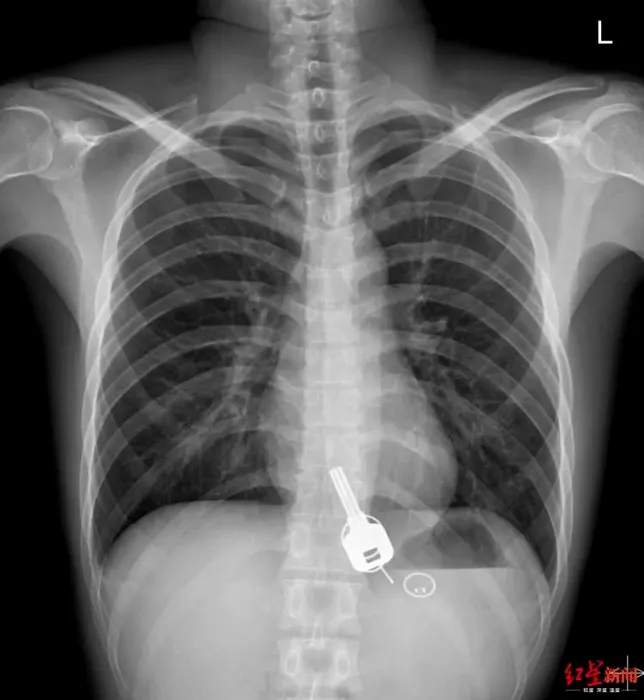

Beție la nivel înalt: S-a trezit cu o durere de stomac, dar când a ajuns la spital medicii i-au găsit un obiect pe care bărbatul îl credea pierdut – FOTO